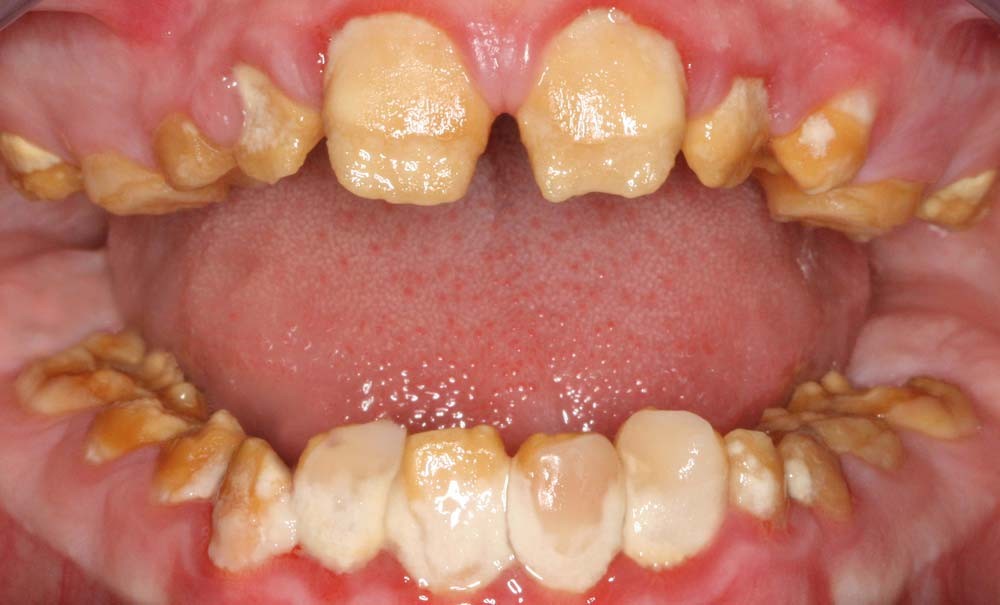

Forme sévère d’amélogenèse imparfaite : prise en charge pluridisciplinaire et réhabilitation céramo-céramique

Une perturbation de l’amélogenèse peut se traduire par une réduction de la quantité d’émail et/ou une altération de sa minéralisation et de sa maturation. Ainsi, les défauts amélaires sont variables et subdivisés en forme hypoplasique (la plus fréquente), hypomature, ou hypominéralisée (plus rare) et peuvent exister de manière isolée ou associée à d’autres symptômes dans le cadre de syndromes [5].

Les principales conséquences sont une usure dentaire rapide et une altération de l’esthétique perturbant la qualité de vie des patients atteints. D’autres caractéristiques cliniques sont fréquentes telles que des retards d’éruption, des agénésies, des calcifications pulpaires, une résorption progressive, des racines courtes ou très longues [6,7].

Certaines caractéristiques cranio-faciales peuvent également être présentes comme une endomaxillie, une courbe de Spee inversée et une infraclusion antérieure (béance). Les patients éprouvent parfois des difficultés à la mastication en raison d’une hypersensibilité et d’une perte de dimension verticale d’occlusion (DVO) engendrées par l’attrition [8,9].